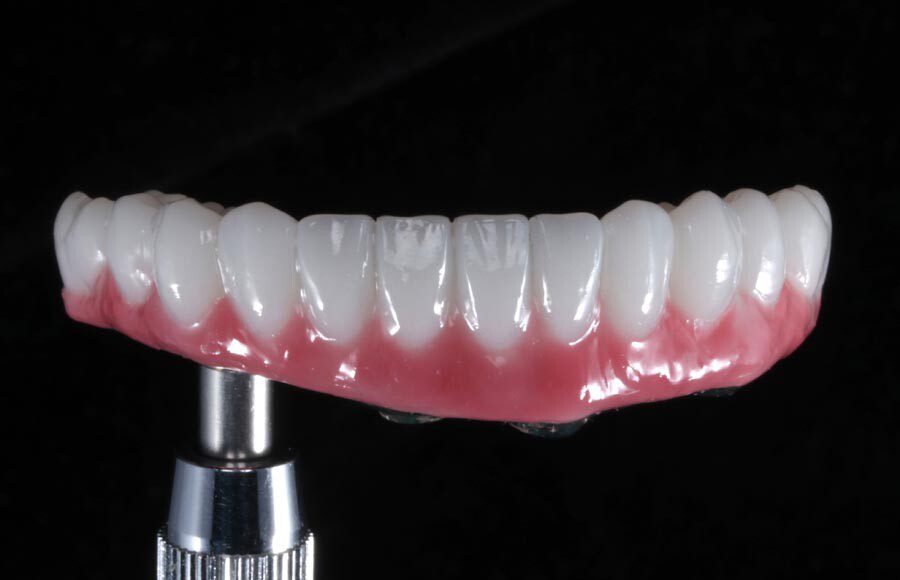

Smile GalleryImplant RestorationsImplant Dentures Post-op smiling 1 of 32 Pre-op close up smiling Pre-op lips retracted smiling Pre-op panoramic x-ray Implants in upper jaw (occlusal view) Implants in lower jaw (occlusal view) Panoramic x-ray of implants First set of try-ins – upper denture First set of try-ins – lower fixed provisional Delivered try-ins (lips retracted) Close adaptation to gums and appropriate emergence profile of lower fixed provisional Gum tissues have been molded by a convex provisional Delivered try-ins Second set of try-ins (lips retracted) Close adaptation to gums and appropriate emergence profile of second set of lower fixed provisional Delivered second try-ins Definitive restorations on casts (frontal view) Definitive restorations on cast (right side) Definitive restorations on cast (left side) Definitive upper overdenture (occlusal view) Definitive lower fixed titanium-acrylic hybrid restoration (occlusal view) Definitive lower fixed titanium-acrylic hybrid restoration (frontal view) Definitive lower fixed titanium-acrylic hybrid restoration (tissue side view) Healthy molded gum tissues on lower prior to delivery of lower fixed hybrid restoration Healthy gum tissues on upper prior to delivery of upper overdenture Definitive restorations (frontal, lips retracted) Definitive lower restoration (frontal) Definitive restorations (right side) Definitive restorations (left side) Definitive lower restoration (occlusal view) Definitive upper restoration (occlusal view) Post-op panoramic x-ray Post-op smiling